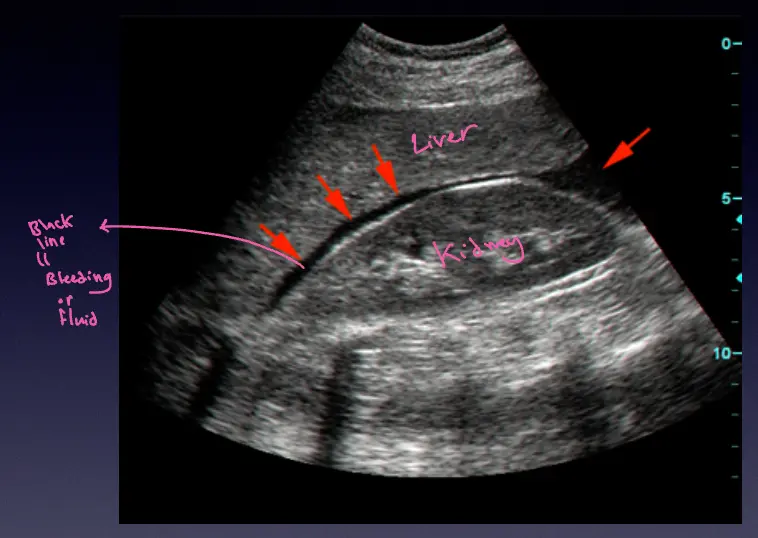

RUQ Scan (Morrison’s Pouch)

Liver and Kidney interface.

normal

Normal Morrison’s pouch.

bleeding